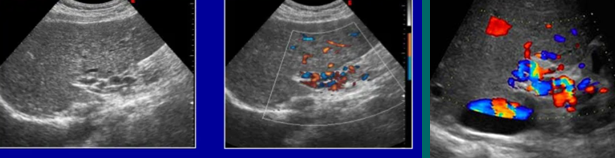

portosystemic venous collaterals